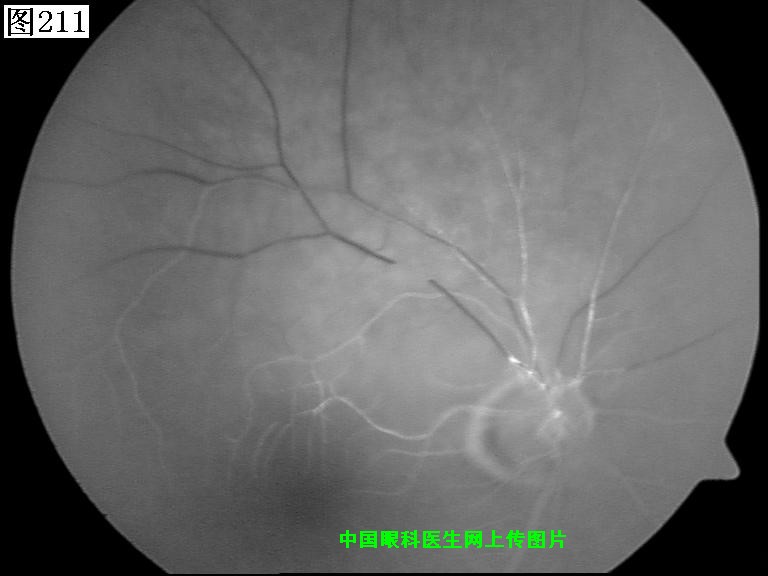

209 210 211 212